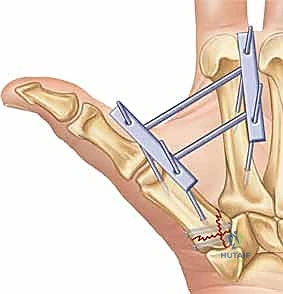

1. الرد المغلق والتثبيت عبر الجلد بالإبر (CRPP - Closed Reduction and Percutaneous Pinning)

هذا الإجراء هو الخيار المفضل لكسور "بينيت" التي يمكن إعادتها لمكانها بدون فتح جراحي كبير.

* الخطوات: يتم إجراء العملية تحت التخدير الموضعي أو الكلي. باستخدام جهاز الأشعة السينية المباشر في غرفة العمليات (C-arm Fluoroscopy)، يقوم البروفيسور هطيف برد الكسر إلى مكانه المثالي.

* بعد ذلك، يتم إدخال إبر معدنية دقيقة (K-wires أو Kirschner wires) عبر الجلد مباشرة لتثبيت قاعدة المشط الأول بالعظم المربعي، وأحياناً بالمشط الثاني لزيادة الاستقرار.

* الميزة: شقوق صغيرة جداً، ألم أقل، وشفاء أسرع. يتم إزالة هذه الإبر عادة في العيادة بعد 4 إلى 6 أسابيع.